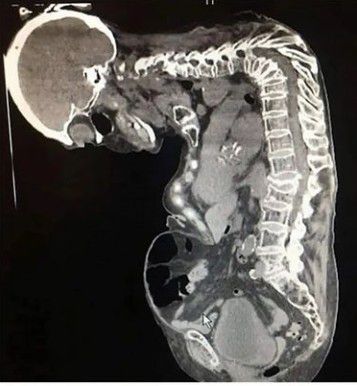

It is characterized by the collapse of the anterior portion of one or more vertebral bodies, resulting in kyphosis.⠀ ⠀ ⏩Gibbus deformities arise most commonly from tuberculosis infection of the spine in the thoracic region but may also result from congenital anomalies including horseshoe kidney. ⠀ ⠀ ⏩Compression fractures and metabolic diseases such as mucopolysaccharidoses or cretinism have been implicated in the development of Gibbus deformities⠀ ✅Infection, congenital abnormalities, and metabolic disorders lead to bone weakness making vertebral bodies vulnerable to collapse⠀ ⠀ ⏩Preferential collapse of the anterior vertebral body leads to a wedge shape and progressive kyphosis characteristic of Gibbus deformities. Progressive kyphosis risks cord compression, myelopathy, and paraplegia if untreated⠀ ⠀ ⏩Treatment for Gibbus deformity, caused by infectious sources, requires both antibiotics to treat osteomyelitis as well as surgical correction which usually involve corpectomy, interbody cage placement, and posterior instrumentation and fusion. ⠀ ⠀ ⏩If treated promptly, patients typically improve following surgical correction, with one study demonstrating improvement in postoperative intervertebral height and kyphotic angulation correction from 2.1° to 27.1°⠀ ⠀ ⏩Treatment options differ between children and adults. Adults are commonly treated with posterior fusion with or without corpectomy and interbody cage placement, while surgery in children usually involves vertebral column resection and cage insertion with placement of bilateral vertical expandable prosthetic titanium ribs or rods. By: https://www.instagram.com/p/CeOF-3YhYki/?igshid=YmMyMTA2M2Y=